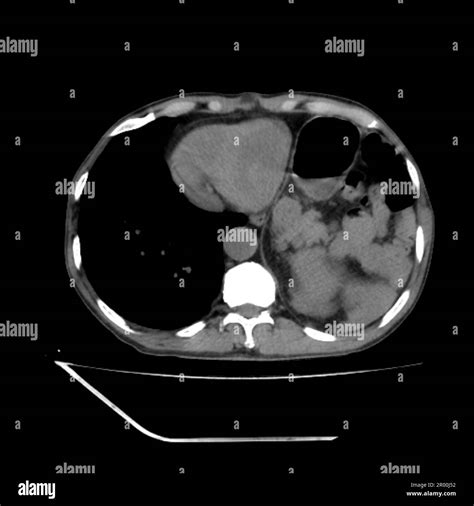

A Ct Scan En Español is a diagnostic imaging procedure that uses a combination of X-rays and computer technology to produce cross-sectional images of the body. These images provide detailed views of organs, bones, and other internal structures, allowing healthcare providers to detect abnormalities, injuries, and diseases with high accuracy.

• Scanning: The patient lies on a table that slides into the CT scanner, a large, doughnut-shaped machine. The scanner rotates around the body, taking multiple X-ray images from different angles.

• Image Processing: The images are then processed by a computer to create detailed cross-sectional views of the body.

Liver Masses CT scans can detect masses and cysts in the liver, which may be benign or malignant.

Internal Bleeding CT scans can detect internal bleeding, which may be life-threatening if not treated promptly.